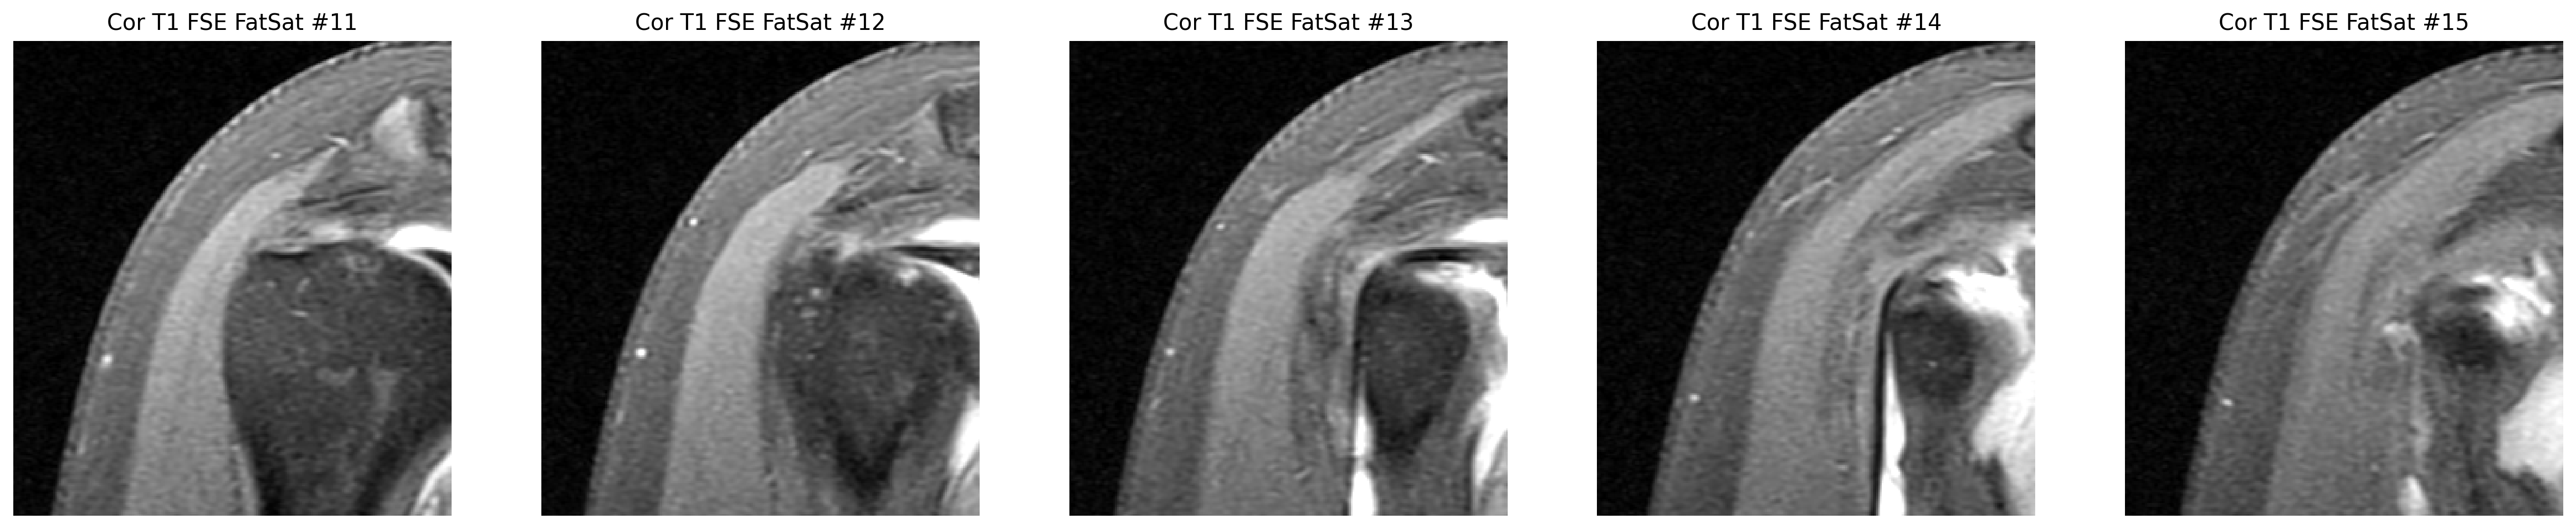

Focused coronal look at the supraspinatus footprint.

The cuff finding was checked in coronal and sagittal views, while the labrum was reviewed on axial arthrogram slices.